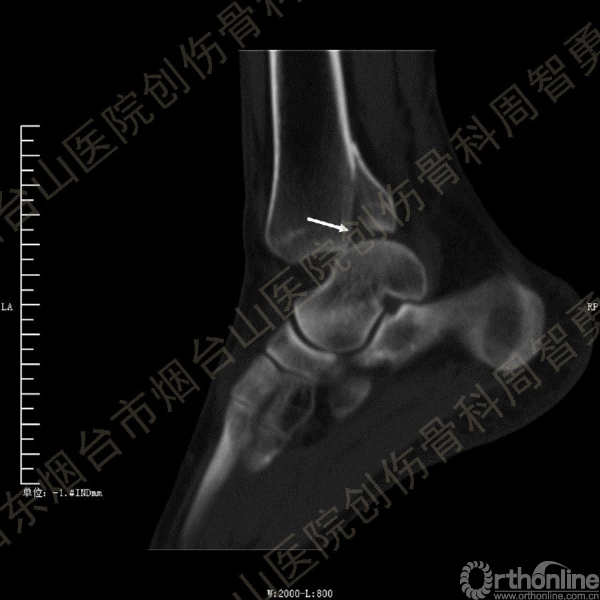

患者一般情况可,左踝关节肿胀,见皮下瘀斑,内、外、后侧有压痛,左踝关节主动运动受限,左足皮肤感觉、血供未见明显异常,左足趾各关节可主动运动。左踝关节正位X线片和CT重建示内踝内上方双层骨皮质影(图1a,c),CT示后侧骨折块分为后内侧骨折块和后外侧骨折块(图2a,b),后内侧骨折块累及内踝后丘,后丘骨折线呈冠状位(图2c),后内侧骨折块腹侧有向近端塌陷的小块骨软骨骨折块(图2d),CT也显示Chaput骨折块(图1c,2e)。

经典的后踝骨折发生于低能量旋转外力所致的踝关节骨折;标准pilon骨折见于高能量轴向暴力;而后侧pilon骨折是旋转外力和轴向暴力共同作用的结果,属于中等能量的损伤。踝关节骨折中的后踝骨折源自下胫腓后韧带的牵拉,骨折块位于后外侧,常为单一的三角形骨折块,大小从关节外片状骨折到累及胫骨远端关节面矢状径的40%(图4a)。后侧pilon骨折中的后侧骨折块较大,累及内踝后丘(三角韧带深层起点)在内的整个胫骨远端后侧,分为后内侧骨折块和后外侧骨折块,后内侧骨折块腹侧有向近端塌陷的骨软骨骨折块(图4b)。后侧pilon骨折中的内踝骨折线并不是水平位而是冠状位,可合并内踝前丘骨折。后侧pilon骨折踝关节正位X线片示特异性的内踝内上方双层骨皮质影(图1a,c)。这是由于后内侧骨折块的骨折线延伸到胫骨远端骨骺和干骺端的内侧骨皮质,其移位后的边缘成像所致。水平位CT显示后侧骨折块分为后内侧骨折块和后外侧骨折块,矢状位CT示后内侧骨折块腹侧有向近端塌陷的骨软骨骨折块。

③影像表现:踝关节正位X片显示特异性的内踝内上方双层骨皮质影

↑图 1a

↑图 1b

↑图 1c

图 1 术前左踝关节正侧位X线片和CT重建,箭头所示内踝内上方双层骨皮质影(a,c)